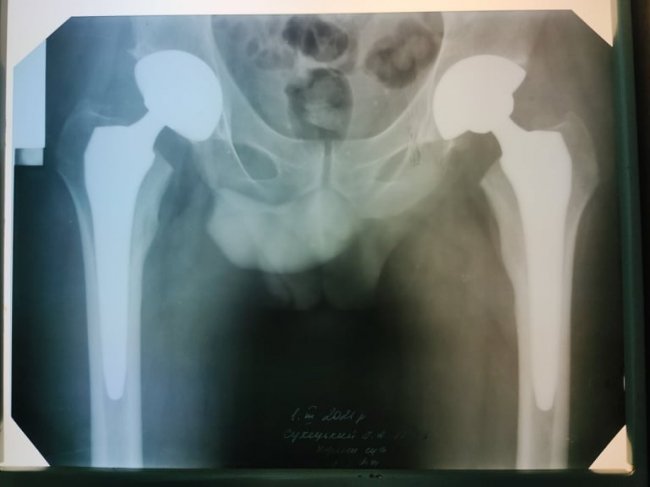

27 лютого хірурги госпіталю замінили 31-річному пацієнту обидва тазостегнових суглоби, які були зруйновані асептичним некрозом. Чоловіку загрожувала важка інвалідність. Операцію зробили, застосовуючи технологію мінідоступів, яка дає можливість уникнути травматизації м’язів, значно зменшити крововтрату та встановити ендопротези через невеликі розрізи менше 10 см.

«Зважаючи на молодий вік чоловіка, ми вирішили застосувати методику SuperPATH. Це мінідоступ з мінімальною травматизацією м’яких тканин. Тобто, розсікається тільки шкіра та підшкірна клітковина, а м’язи розшаровуються, і надсікається верхня частина капсули кульшового суглоба. Це, по-перше, маленький розріз (5 см), невелика крововтрата. По-друге, не травмуються м’язи і хлопець вже в перший день зміг вставати і самостійно йти. На третій день після операції об’єм рухів у нього практично такий, як у здорової людини. Він самостійно встає, ходить. Дякуємо фахівцеві відділення ортопедичної артрології та ендопротезування Інституту патології хребта і суглобів імені професора Ситенка з Харкова, який знайшов можливість приїхати та поділитися з нами своїм досвідом», - каже Олександр Кругляк.

«Асептичний некроз голівок стегнових кісток може бути однобічним, але в цього пацієнта, на жаль, двобічний. Це захворювання виникає, коли тромбуються судини, які харчують кістку і частину голівки. Поступово ця частина голівки відмирає, стає рухлива, що завдає хворому болю, і людина стає, фактично, інвалідом. Враховуючи молодий вік і участь в АТО, то це може бути пов’язано. Якщо узяти розгрузку, бронежилет і зброю, яку він носив, це виходить доволі значна вага. Тим більше, що її не просто треба носити, а й стрибати з БТРа, наприклад. Усе це надлишок навантаження, який може призвести до захворювання. Однак захворювання може виникнути навіть і після грипу, після гнійно-запального чи просто запального захворювання, наприклад, ангіни, яке призводить до згортання крові, а цей фактор може в подальшому спровокувати асептичний некроз», - зауважує лікар.